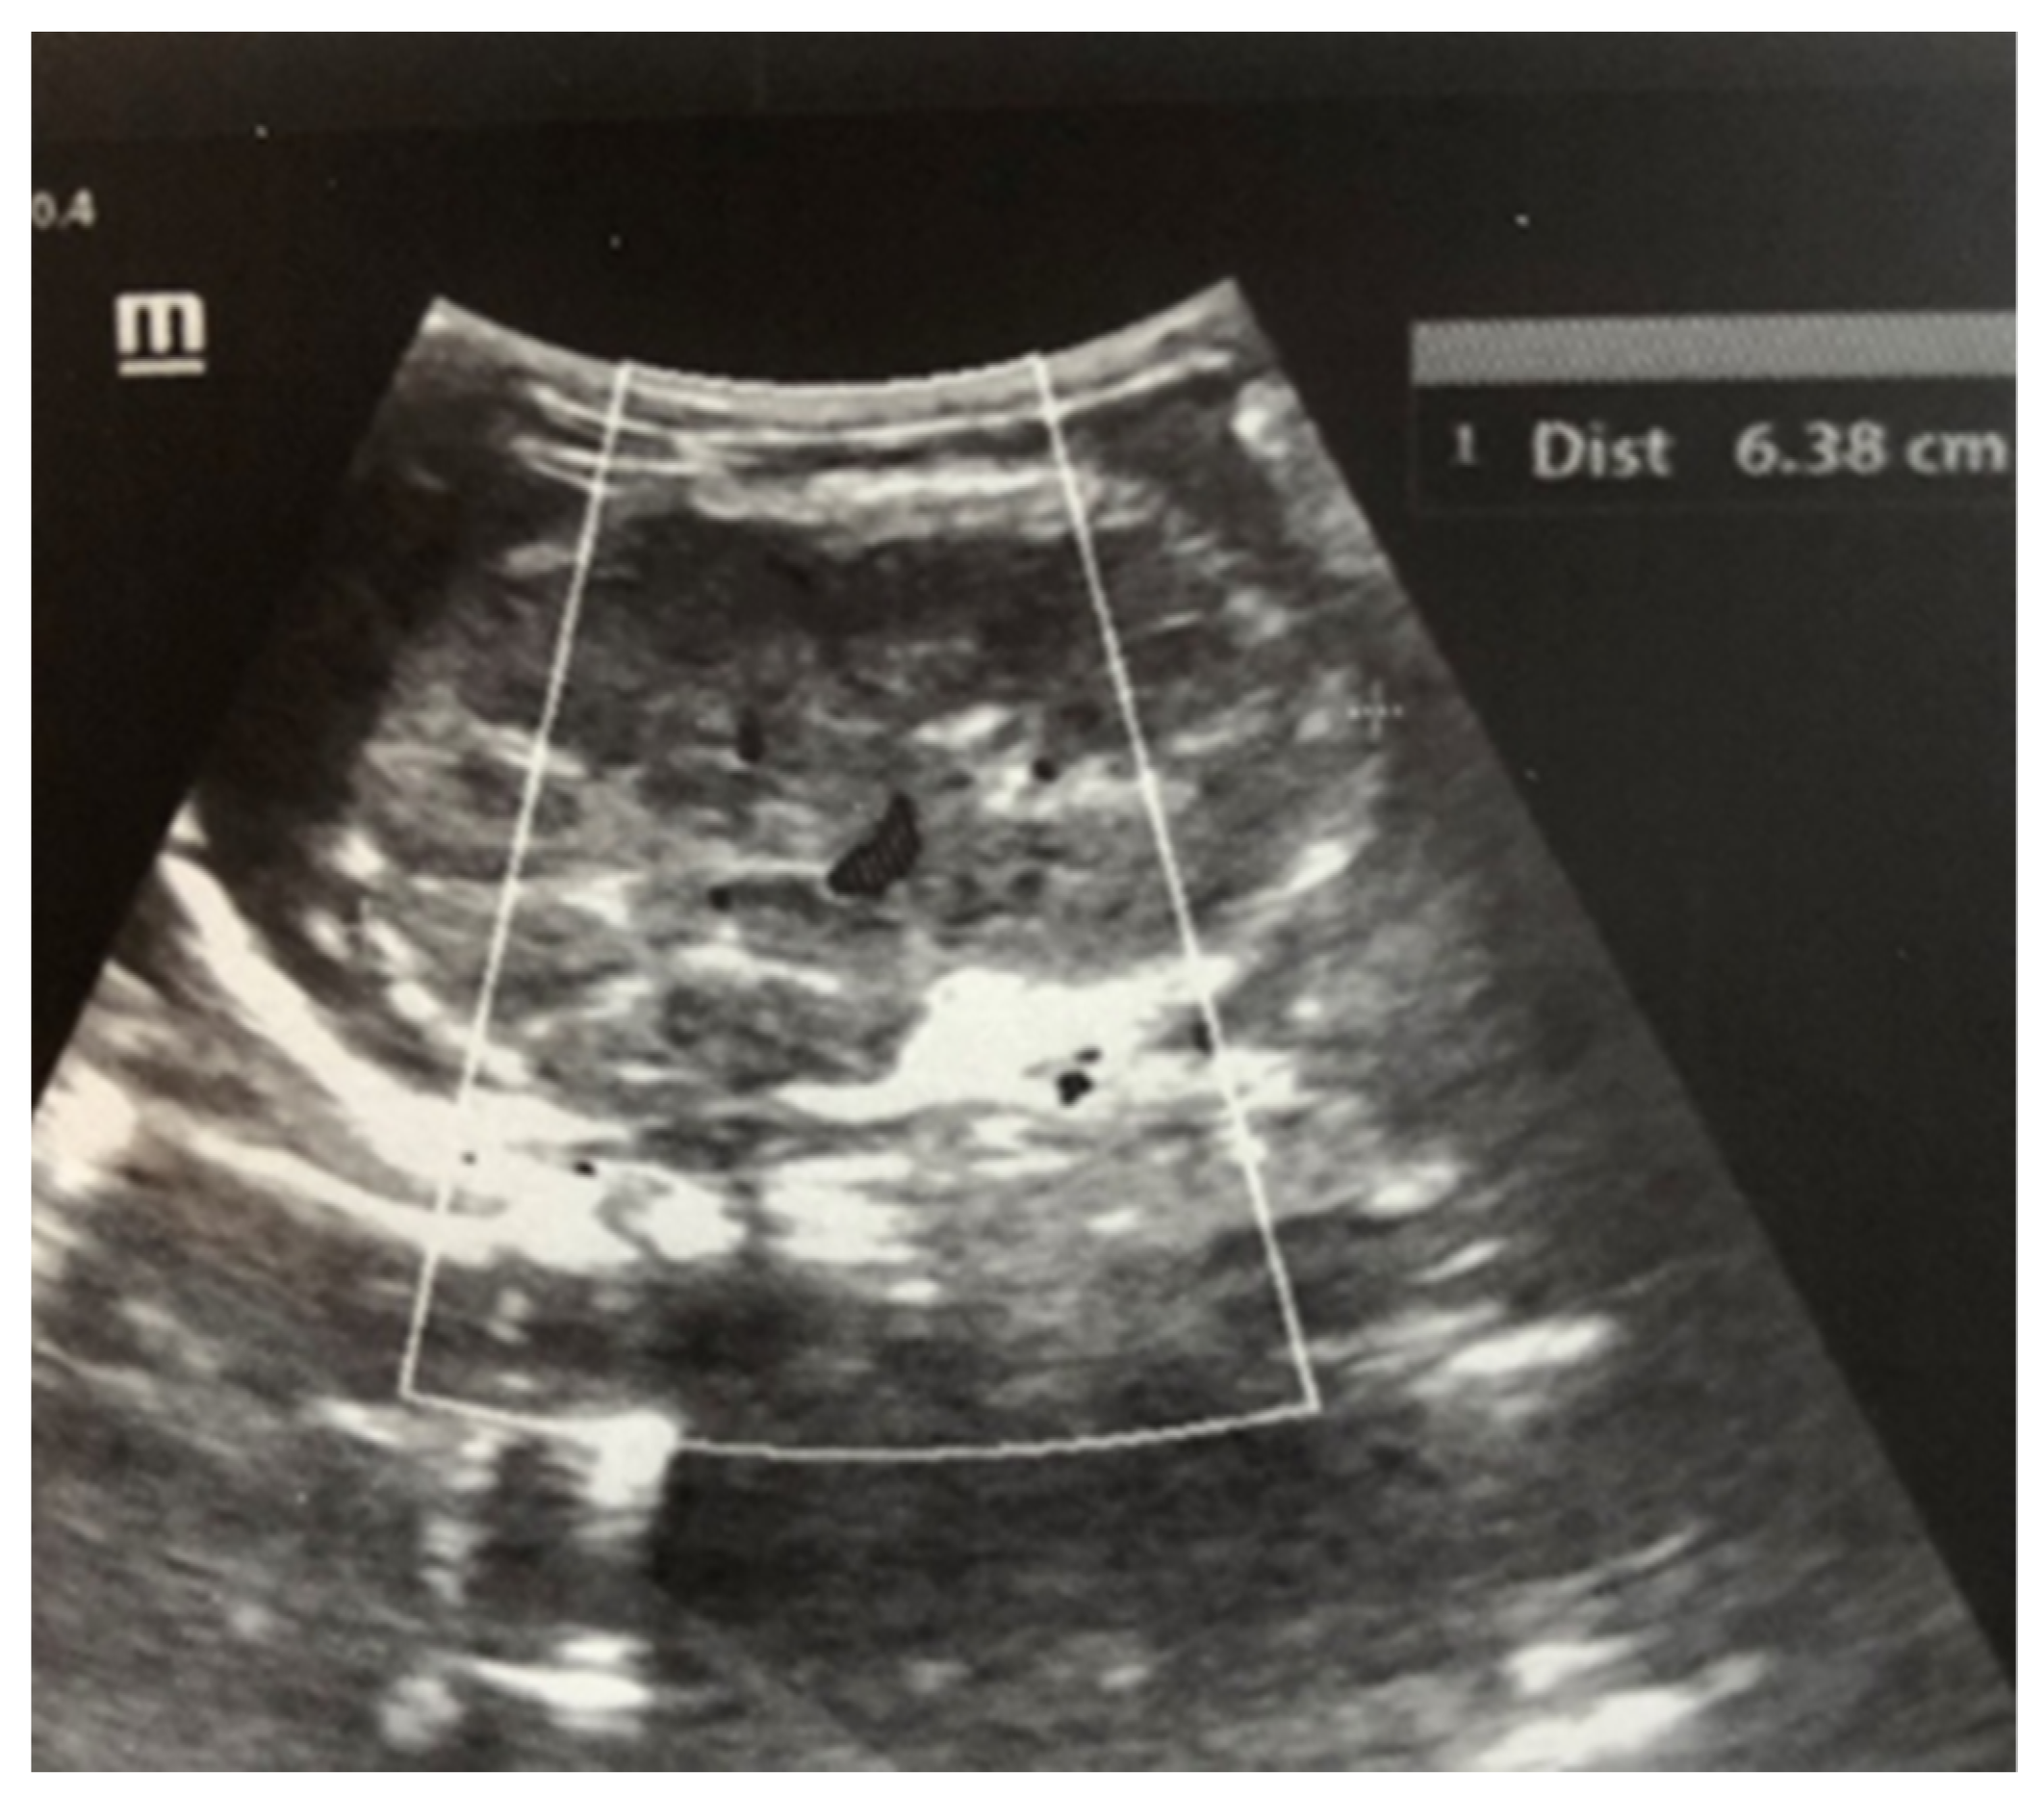

After admission to the NICU, the neonate was found febrile, with symptoms of multiple organ failure: respiratory system failure requiring treatment with Curosurf and mechanical ventilation; renal failure with symptoms of oliguria, macroscopic hematuria, and an increase in nitrogen waste products; the manifestation of neurological symptoms—muscular hypertonia and hyperreflexia, increased convulsive readiness with frequent spontaneous and provoked clonuses of the limbs. The blood tests revealed inflammatory activity—increased CRP and evidence of early nonconjugated hyperbilirubinemia. An abdominal ultrasound examination, performed 2 h after birth, found an enlarged right kidney with a longitudinal size of 6.1 cm, swollen parenchyma with a thickness of 1.8 cm, and increased echogenicity with the presence of interlobar hyperechogenic spikes—an image characteristic of the early phase of renal vein thrombosis. The left kidney—with a longitudinal size of 4.1 cm—preserved the topic, size, and echogenicity of the parenchyma, without drainage disorders, see Figure 1 and Figure 2.

Figure 1. Right kidney image taken in the 2nd hour after birth. There is an increase in size, increased echogenicity of the parenchyma, and interlobar hyperechoic spikes.